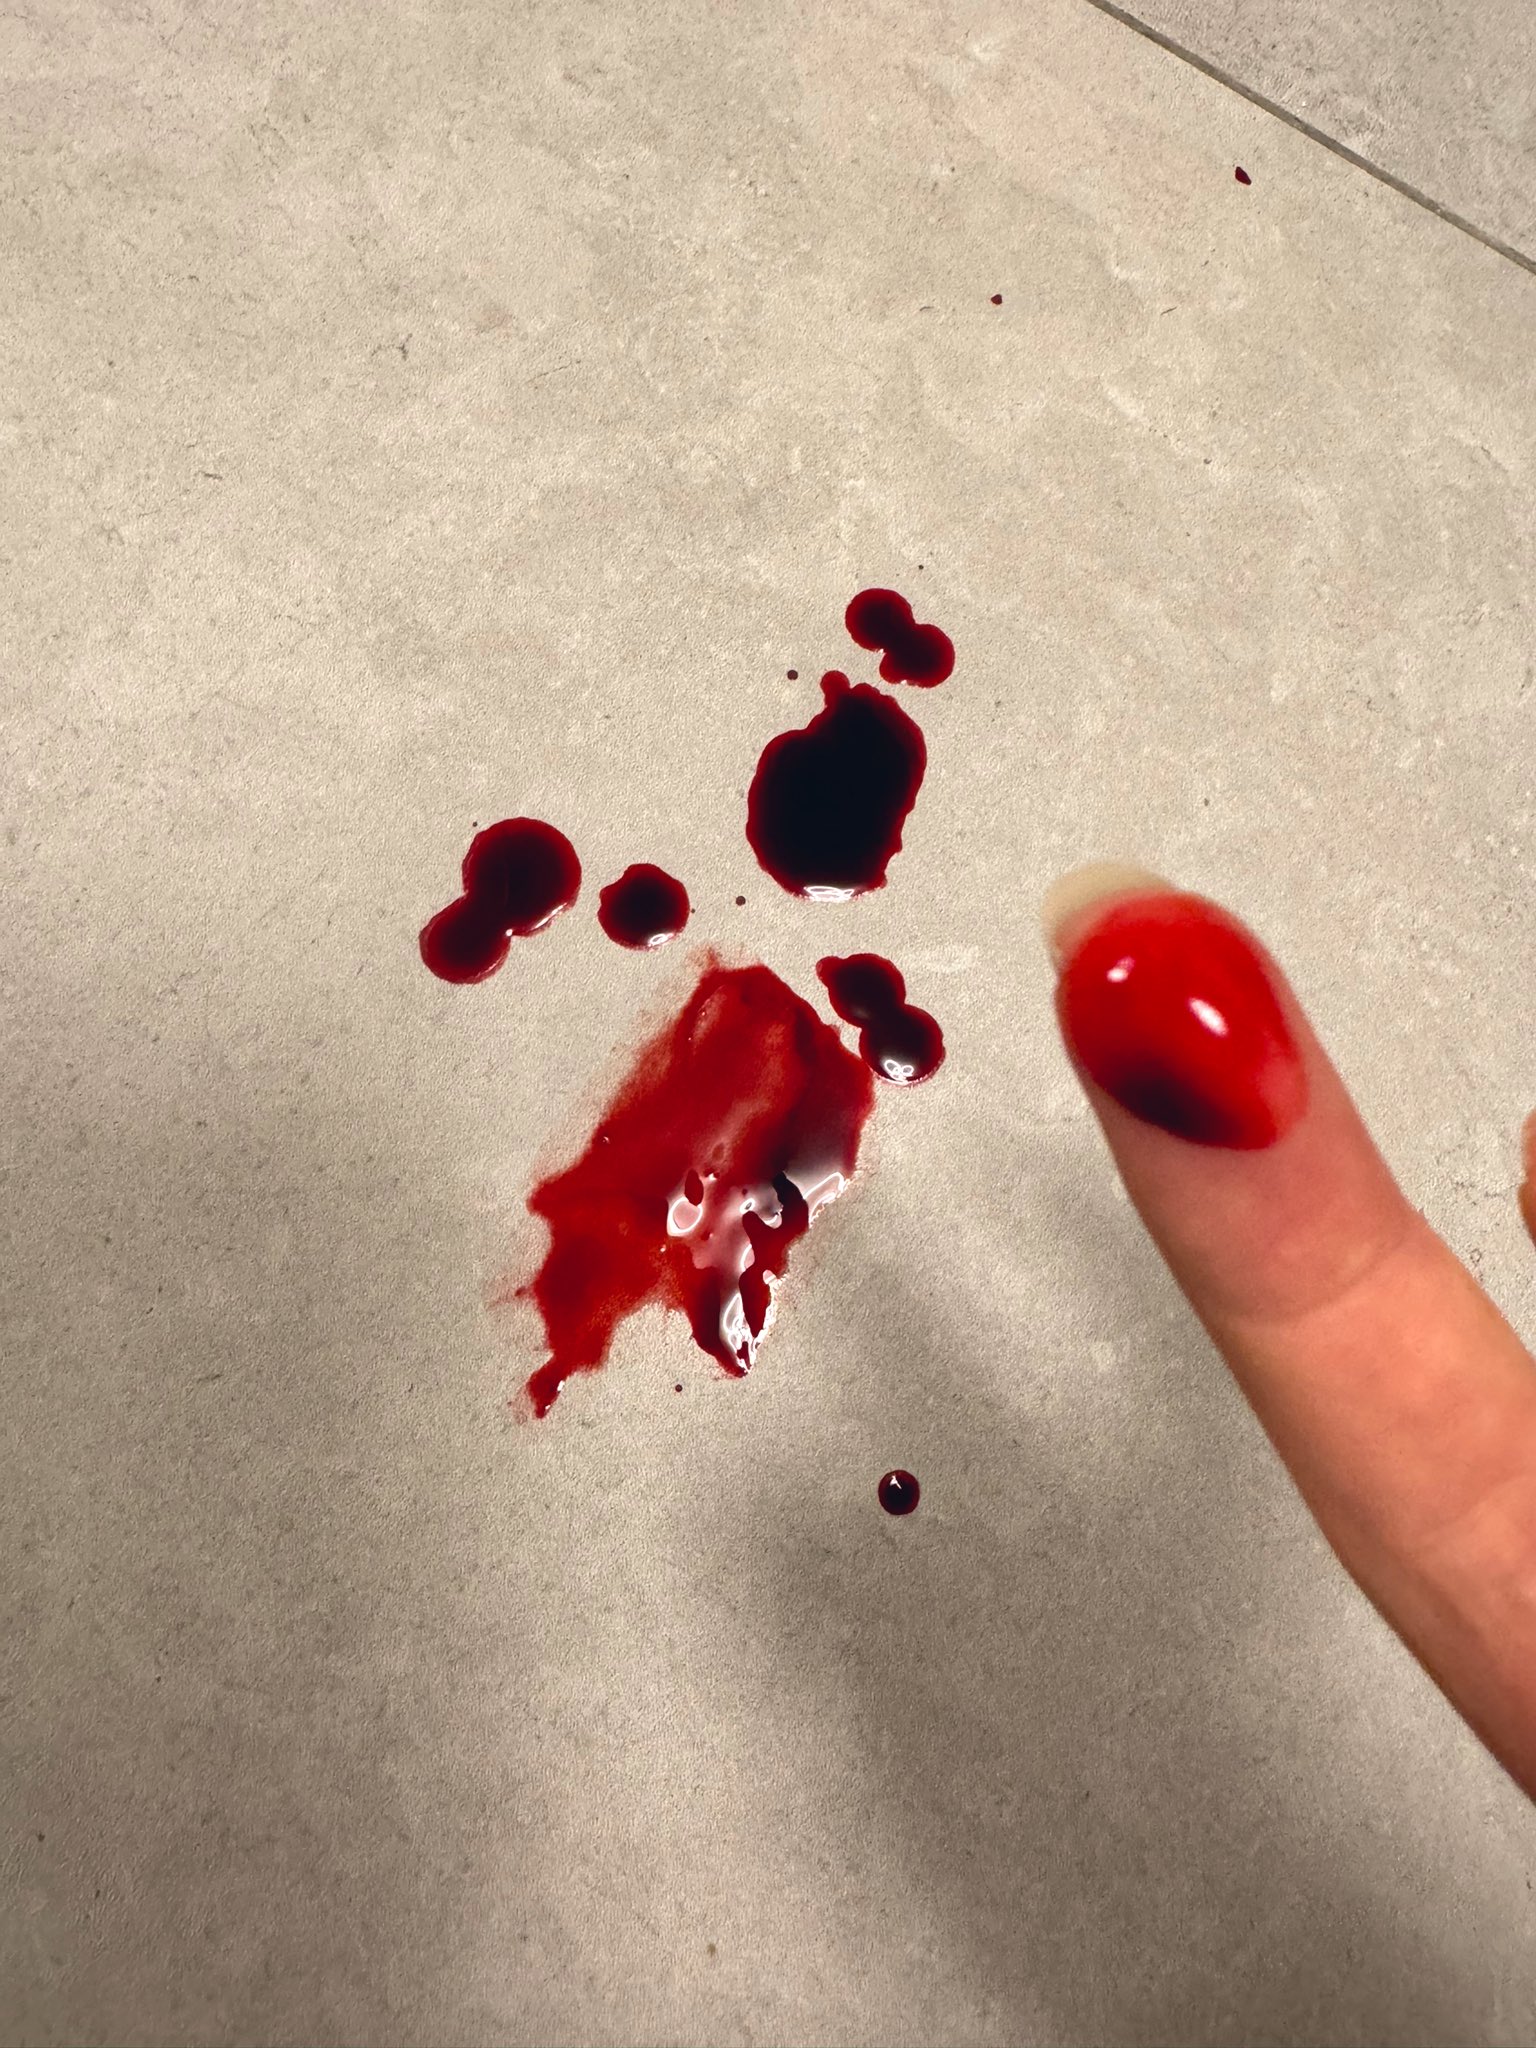

2026-03-04 19:15:41 UTC

本来是1ml,但忘记关闸血液回流,我怕把针管堵了于是又推了1ml

配合另一种麻醉就可以无痛重开了(bushi) https://t.co/Uj139Q2tBk

手上都是血迹不说,周围的其他地方也有我意料之外的血迹

2026-03-04 23:02:13 UTC

炽烈已极 @AnIncandescence嘶。我觉得不行…我没办法维持足够的麻醉深度……啊啊,还要清理织物,这摊到底是怎么搞的

炽烈已极 @AnIncandescence我在一天内逐渐发现了越来越多血迹,床单上被子上衣服上。。🙀要放弃清理了…血液为什么那么难去除啊!